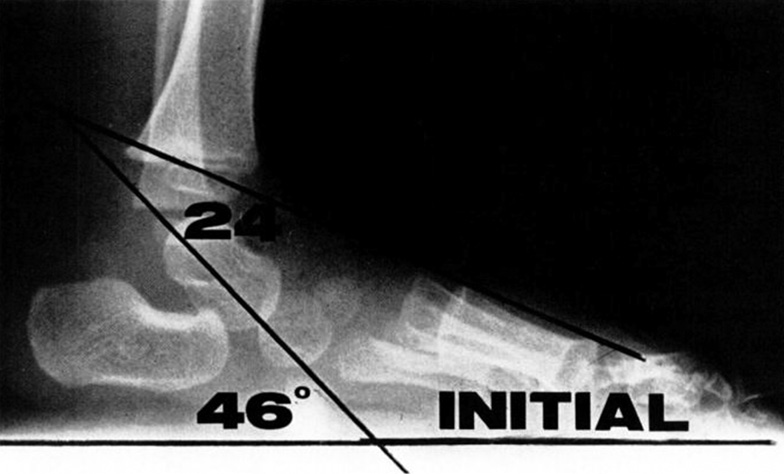

Рентгенографию стоп выполняли в переднезадней и боковой проекциях в положении стоя. Каждый пациент должен был соответствовать одному из двух критериев.

- Угол, образованный таранной костью и основанием стопы (рис. 3-A), — больше 35° (его также называют углом подошвенного сгибания таранной кости [14] и/или таранно-подошвенным углом [13]). Нормальное значение этого угла у детей составляет 26,5 ± 5,3°.

- Угол, образованный таранной и I плюсневой костями (см. рис. 3-A), — больше 10°. В норме этот угол составляет 0° или имеет небольшое отрицательное значение [5, 13]. При кавусной стопе значение угла выраженно отрицательное. Плоскостопие, которое ассоциируется с провисанием на уровне таранно-ладьевидного и ладьевидно-клиновидного суставов, характеризуется положительным значением этого угла.

Рис. 3-A. Типичный пациент. Исходная рентгенография стопы в положении «стоя», боковая проекция: таранно-подошвенный угол (46°) и угол между таранной и I плюсневой костями (24°)